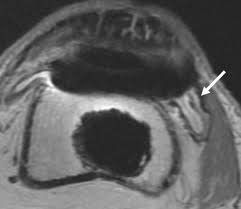

(OSTEOMYELITIS) is a serious condition in which bone gets infected.

Infection could be due to bacteria or fungus.